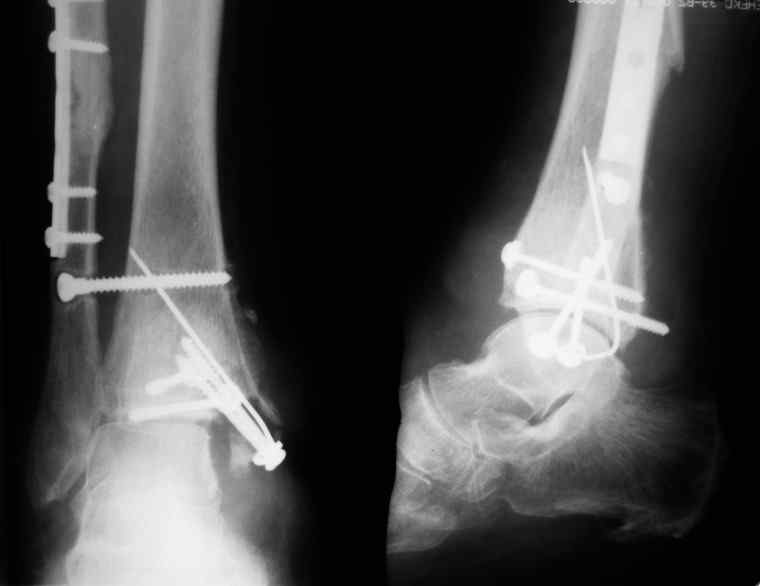

31 августа 2007 года была оперирована в другой области по поводу DS Закрытого двухлодыжечного перелома правой голени с подвывихом стопы кнаружи , кзади. Разрыв дистального межберцового синдесмоза. Перелом заднего края большеберцовой кости справа. Поступила в наше отделение со швами ,с некрозом медиальной поверхности правого голеностопного сустава. Проведено : снятие швов , антибиотики , некрэктомия с последующей кожной пластикой .Заживление 20 декабря 2007 года ,выписана из стационара . 3 марта 2008 года поступает с гиперемией , отек , флюктуацией. В настоящее время имеется рана по медиальной поверхности правой голени ,отеки и гиперемия сохраняется .Наша тактика:1) снятия воспалительного процесса, 2) удаление металлоконструкции, 3) выполнения артродеза правого голеностопного сустава.

Алексей20 15 Март 2008, 14:03

Не очень удачный вариант остеосинтеза: сохранен подвывих стопы, синдесмоз не достаточно репонирован. Думаю, в данном случае у пациента д-з: остеоартрит правого голеностопного сустава, послеоперационный остеомиелит правой голени. Предлагаю тактику: одномоментно выполнить удаление металлоконструкции, хирургическую обработку очага остеомиелита, резекцию голеностопного сустава, артродез аппаратом. Другие методы лечения не привидут к купированию гнойного процесса. Так как полость сустава в настоящее время имеет вид пиогенной капсулы, в которой будет поддерживаться гнойный процесс даже после заживления свища, с последующим его открытием и опорожнением гноя.